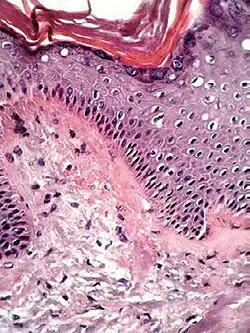

| Lichen planus | Irregular epidermal hyperplasia with a jagged “sawtooth” appearance, compact hyperkeratosis or orthokeratosis, foci of wedge-shaped hypergranulosis, basilar vacuolar degeneration, slight spongiosis in the spinous layer, and squamatization. The dermal papillae between the elongated rete ridges are frequently dome shaped. Necrotic keratinocytes can be observed in the basal layer of the epidermis and at the dermal-epidermal junction. Eosinophilic remnants of anucleate apoptotic basal cells may also be found in the dermis and are referred to as “colloid or civatte bodies”. Whickham striae are usually seen in the areas of hypergranulosis. Vacuolar degeneration at the basal layer may be noted leading to focal subepidermal clefts (Max Joseph spaces). Squamatization occurs as a result of maturation and flattening of cells in the basal layer. It happens in areas of marked hypergranulosis with prominence of the sawtooth pattern of rete ridges. Wedge-shaped hypergranulosis can occur in the eccrine ducts (acrosyringia) or hair follicles (acrotrichia). In the hypertrophic subtype, the associated hyperkeratosis, parakeratosis, hypergranulosis, papillomatosis, acanthosis, and hyperplasia markedly increased with thicker collagen bundles forming in the dermis. Moreover, the rete ridges are more elongated and rounded as opposed to the typical sawtooth pattern. In atrophic LP, loss of the rete ridges and dermal fibrosis is prominent. In vesiculobullous LP, the disease progression is quicker. Hence, some of the distinctive features such as hyperkeratosis, hypergranulosis, or dense lymphocytic dermal-epidermal infiltrate may not be present. LP lesion may resolve with residual hyperpigmentation caused by a persistent increase in the number of melanophages in the papillary dermis.[9] | ![]() |